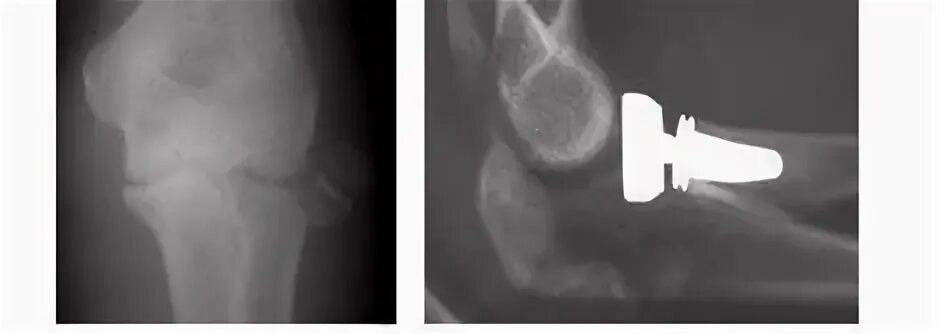

Полное расхождение суставных